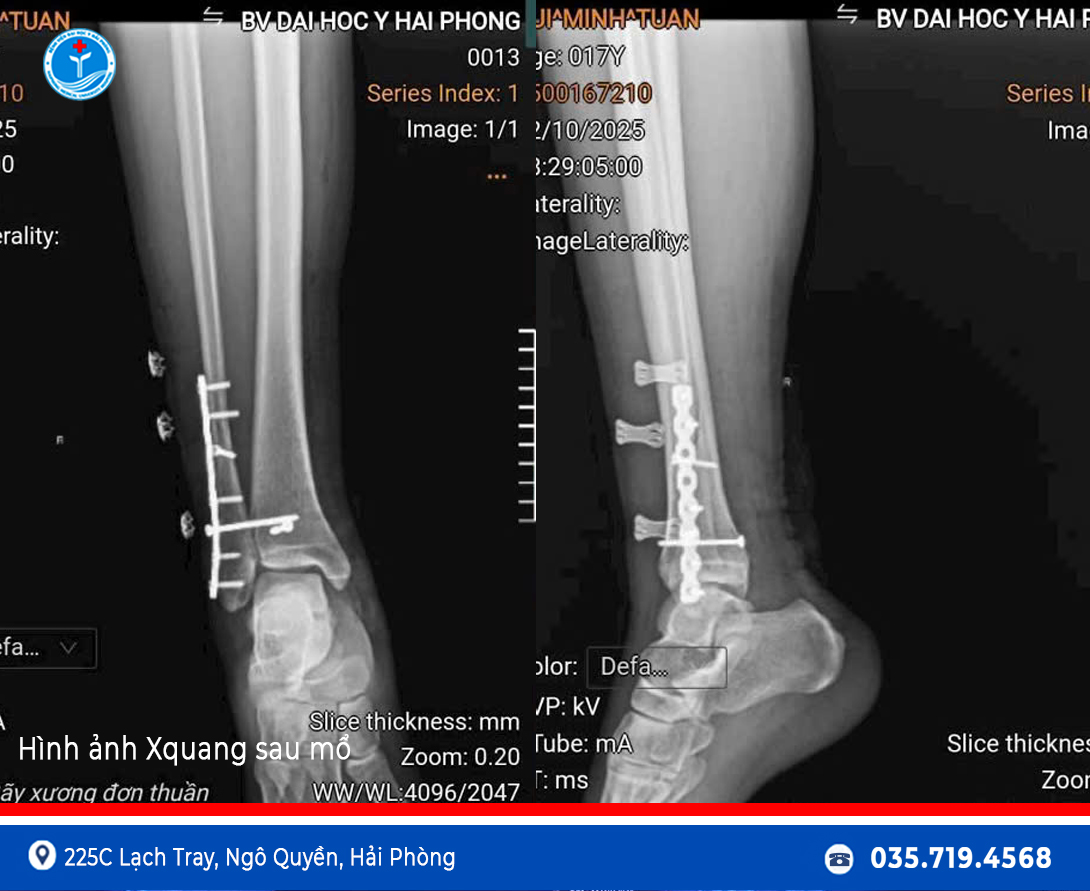

Kết quả hội chẩn cho thấy bệnh nhân bị gãy kín đầu dưới xương mác, gãy kín mắt cá sau và trật khớp cổ chân phải, chỉ định phẫu thuật kết hợp xương và nắn chỉnh trật khớp sớm để đảm bảo phục hồi chức năng vận động.

Nhờ sự phối hợp nhanh chóng, hiệu quả giữa hai bệnh viện, bệnh nhân đã được chuyển tuyến an toàn và Bệnh viện Đại học Y Hải Phòng tiếp nhận, tiến hành phẫu thuật chỉ sau hơn 1 giờ kể từ khi chấn thương.

Ca phẫu thuật diễn ra thuận lợi và thành công, sau mổ bệnh nhân giảm đau rõ rệt, vận động được cải thiện và đang phục hồi tốt.